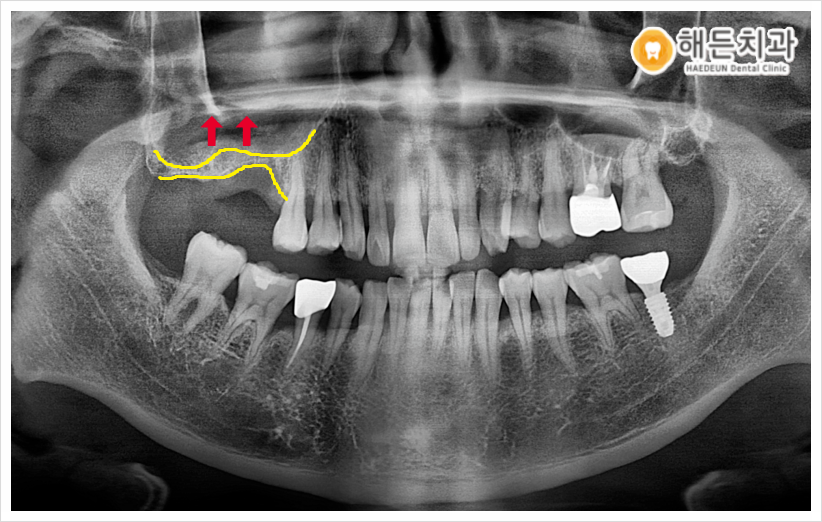

정밀한 검진을 위해, 우선 파노라마 사진을 촬영해 확인해보았습니다.

치아가 상실된 부위의 잇몸뼈가 많이 얇고, 또한 상악동이 내려와 있어서 임플란트를 심기에는 잇몸뼈가 충분하지 않았습니다.

이 상태로 임플란트를 식립하게 된다면 픽스쳐(인공치근)의 고정력이 떨어져 흔들리거나 빠질 수도 있기 때문에 환자분의 경우 상악동 거상술+뼈이식을 동반한 임플란트 식립이 필요했습니다.

상악동이란~? 코 옆 양측의 위 잇몸뼈와 광대뼈 사이의 빈 공간으로 상악동막을 들어 올려 뼈를 이식할 공간을 확보한 뒤 인공뼈를 이식하는 술식을 상악동 거상술이라고 합니다.

상악동 거상술 방법으로는 치조정 접근법과 측방 접근법 두 가지가 있는데요.

치조정 접근법은 잔존 잇몸뼈가 4 mm 이상 남아 있는 경우 픽스처를 식립할 자리에 수압이나 기구를 통하여 상악동막을 들어 올려 뼈이식을 진행하는 방법이고,

측방 접근법 반대로 잔존 잇몸뼈가 4 mm 이하로 잇몸뼈가 많이 없는 경우에 옆쪽에서 접근하여 상악동막을 기구를 통해 들어 올려 뼈이식을 하는 방법입니다.